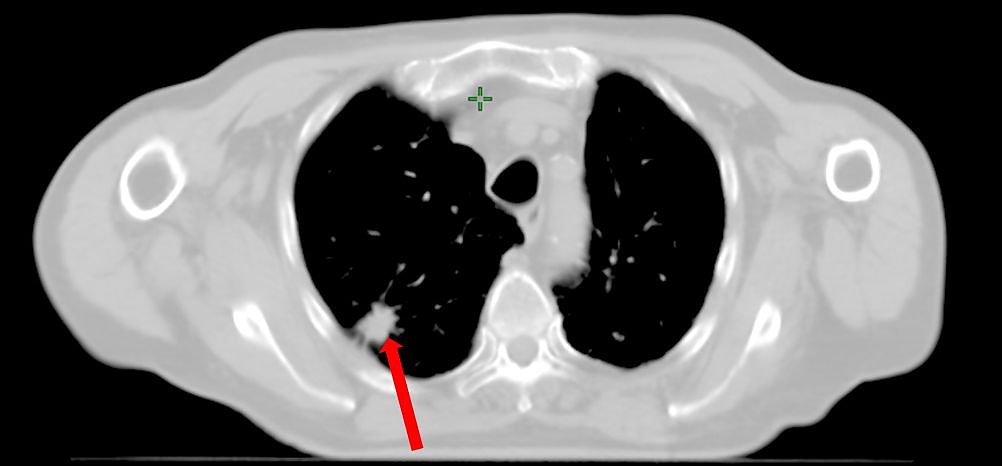

Bei einem Patienten im Nordhäuser Klinikum mit Lungenkrebs wurde diese neue Methode der Bestrahlung bereits erfolgreich angewendet. Der Tumor in der Lunge des Mannes wurde mit einer fünfmal höheren Dosis als normal bestrahlt, dabei lag die Zeit der Bestrahlung nur unwesentlich höher im Vergleich zur normalen Zeit von zwei bis drei Minuten. Für den Patienten ist das alles völlig schmerzfrei.

Nun soll diese Form der Therapie verstärkt bei Patienten angewendet werden, die aus verschiedensten Gründen nicht operabel sind oder die eine Operation ablehnen.